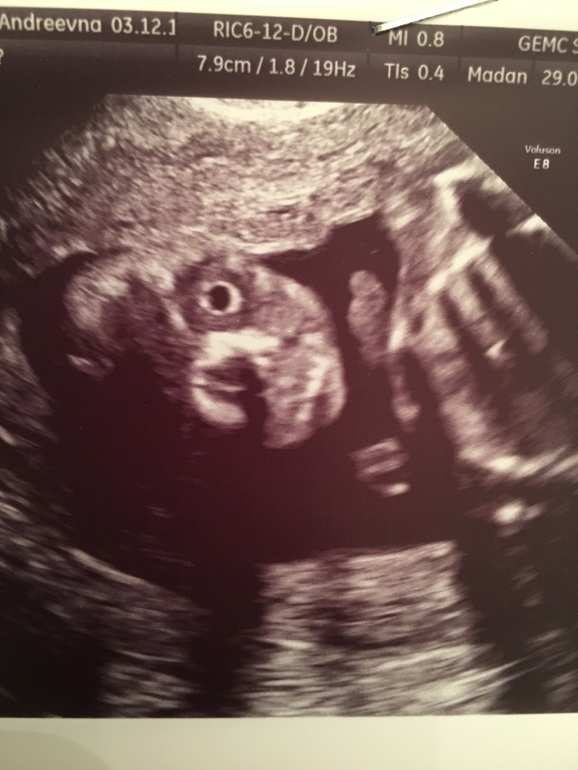

А самое веселое это два хрусталика глаза 👀! Это ужасающее зрелище будто он выпучил глаза и пялится на тебя!

Вот смотрите терминатор ведь!!!(это единственная удачная фото))если ее можно так назвать)